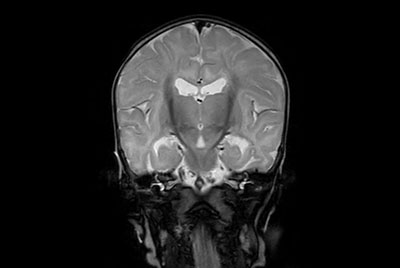

Neonatal Brain